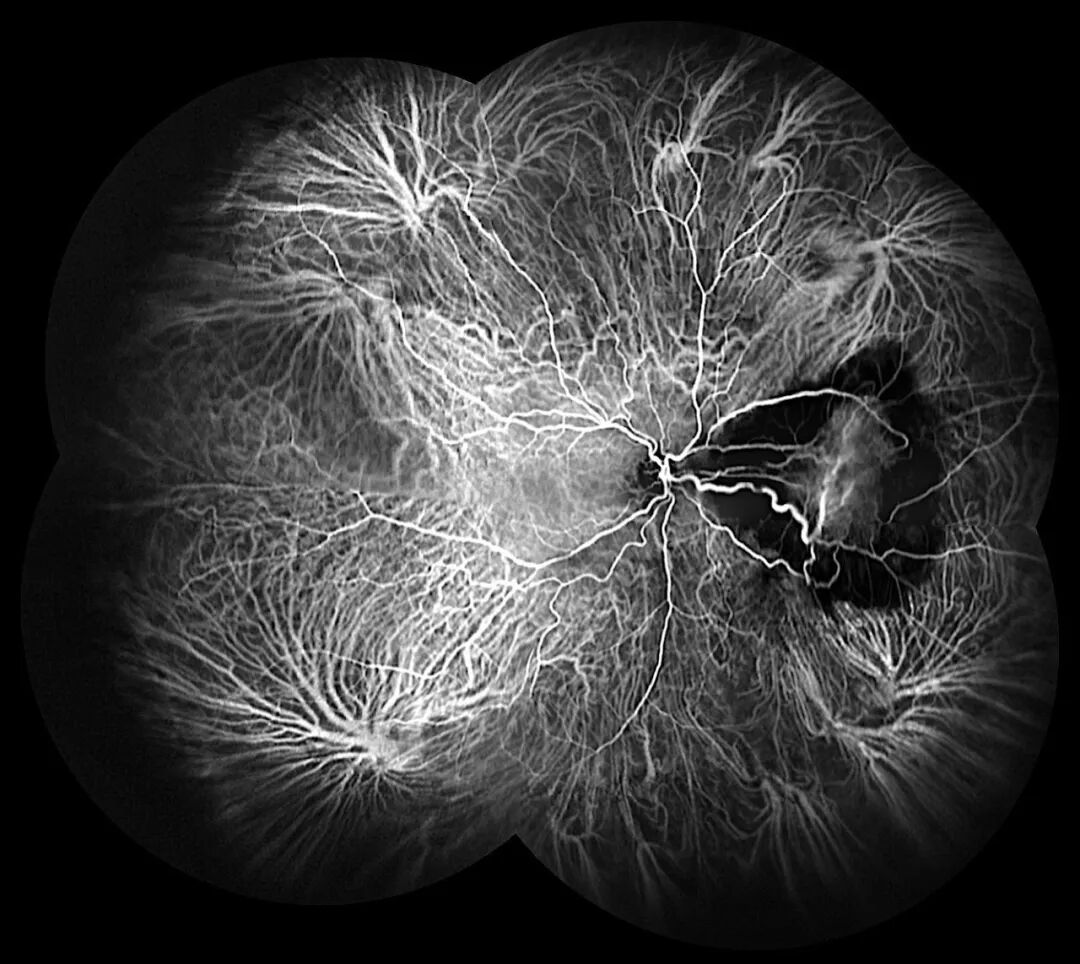

左图:未发现视网膜裂孔

右图:使用广角拼图功能发现视网膜裂孔